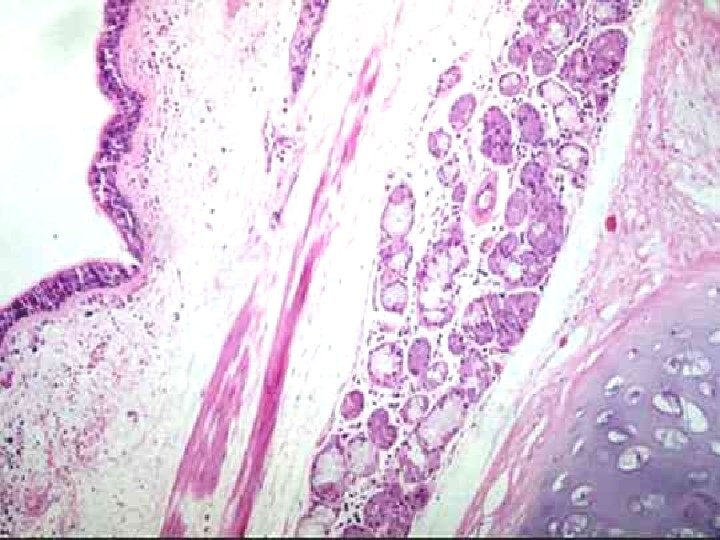

Chronic bronchitis with squamous metaplasia

Chronic bronchitis The lumen of the bronchus is above. Note the marked thickening of the mucous gland layer (approximately twice normal) and squamous metaplasia of lung epithelium.